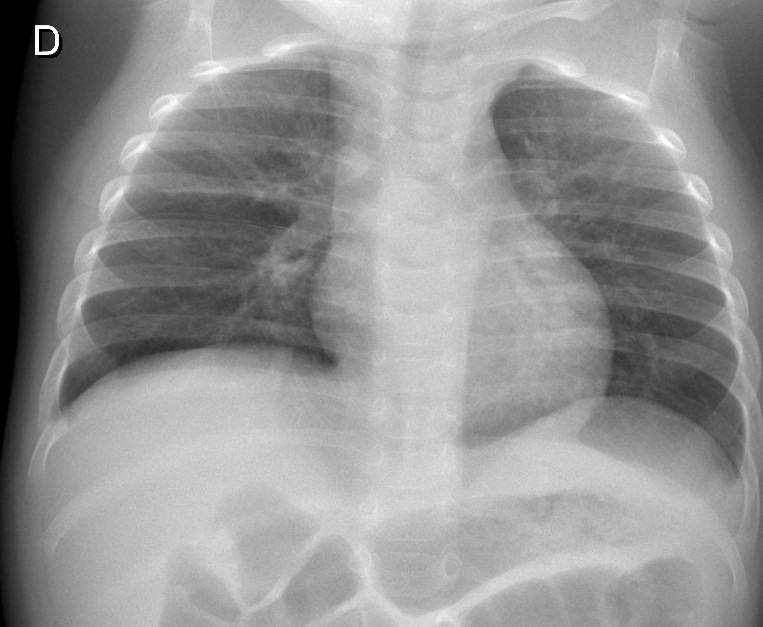

Vous entendez à l’auscultation des crépitants diffus sans foyer, un murmure vésiculaire bien perçu. L’abdomen est souple, il n’y a pas d’hépatomégalie ; les aires ganglionnaires sont libres. Les pouls fémoraux sont perçus. La fontanelle antérieure est normale, l’enfant est fatigué mais reste tonique. Il n’y a pas d’otite ni de purpura